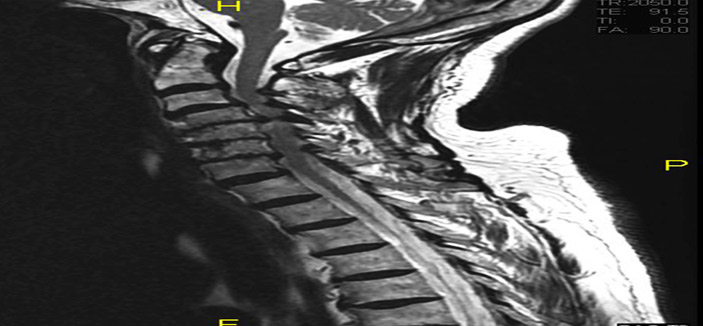

و أوضح الدكتور عبدالله النبهان استشاري جراحة العمود الفقري والمخ والأعصاب والحاصل على الزمالة الألمانية، أن المريض راجع مستشفى جراحة العظام والعمود الفقري، وهو يشكو من فقدان تام للحركة وعدم التحكم التام في حركة اليدين والقدمين ويعاني من تلك الأعراض منذ أكثر من سنة، وعلى الفور رأى فريقنا الطبي ضرورة إخضاع المريض لعملية جراحية مجهرية لتحرير الأعصاب وتوسيع القناة الشوكية.

وأشار الدكتور النبهان إلى أن العملية بدأت بنوع خاص من التخدير لمثل تلك الحالات المعقدة viper optics بحيث يتم منع تحريك العنق تماماً أثناء العملية حتى لا يزيد التضيق، إضافة إلى ضرورة تثبيت المريض على وضعية خاصة تضمن شد العنق وتثبيت الرأس أثناء الجراحة لضمان أفضل النتائج، ومن ثم إجراء الجراحة المجهرية الدقيقة لتحرير العصب وتثبيت الفقرات.